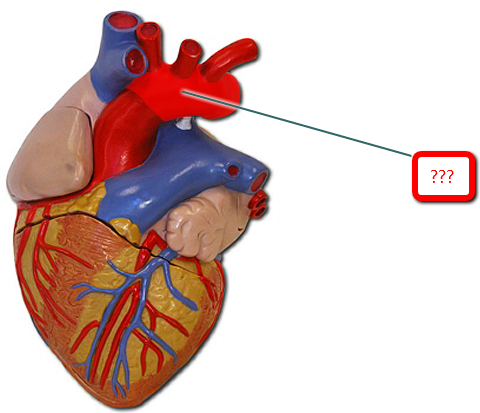

Aortic Arch

Ascending/descending aorta

Brachiocephalic artery

Pulmonary trunk

Superior/inferior vena cava